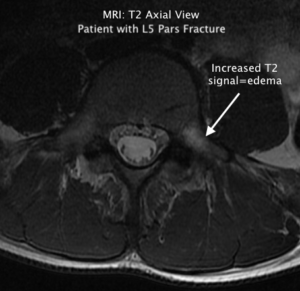

1) For the chiropractor to learn the most common causes, locations, and hallmark x-ray findings of compression fractures and spondylolysis.

II. Spondylolysis